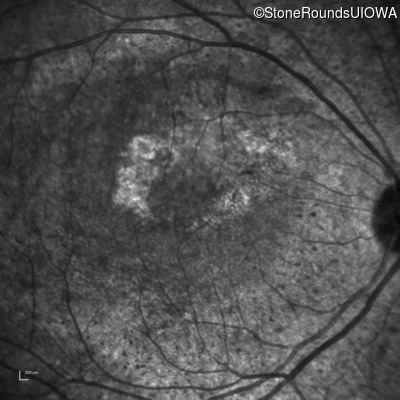

Infrared Fundus Photograph - Right - Count Fingers 1'

Exemplar